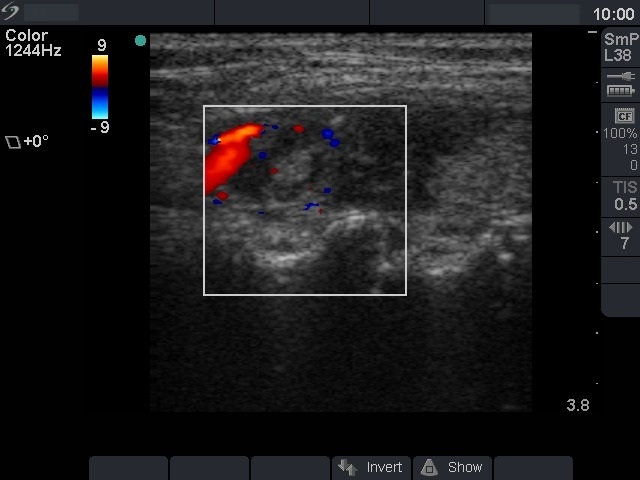

Lymphocytic thyroiditis - case 1440 (ultrasonographic picture 5)

Left lobe, longitudinal scan, power Doppler mode. The vascularity is scanty.